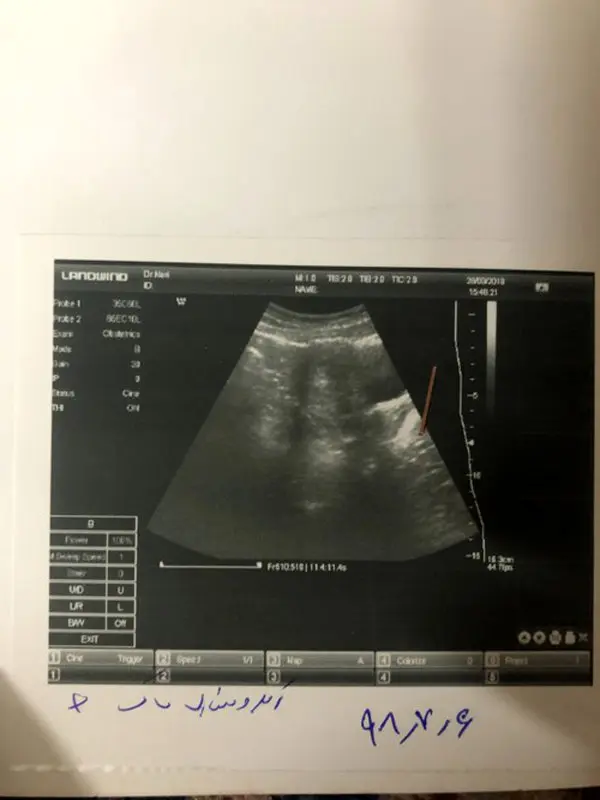

سوال مخاطب نی نی بان: سلام میخواستم بدونم با توجه به عکس سونوگرافی میشه سن بارداری رو گفت؟ و اینکه چقدر وقت دیگه دوباره باید سونوگرافی انجام بدم برای قلب جنین؟ این سونوگرافی توی ۶هفتگی با توجه به اخرین تاریخ پریودم گرفته شده

دوست عزیز به طور کلی مشخص شدن اینکه قلب جنین تشکیل شده یا نه، به چند روش زیر انجام می شود، اگر با سونوگرافی واژینال باشد معمولا بین هفته ۶ بارداری تا هفته ۷ بارداری، از طریق سونوی شکمی یک هفته از روش قبلی دیرتر یعنی بین ۷ تا ۸ هفتگی مشخص می شود و اگر با دستگاه هایی باشد که بخواهید صدای قلب جنین خود را هم بشنوید از ۴ ماهگی به بعد مشخص می شود.